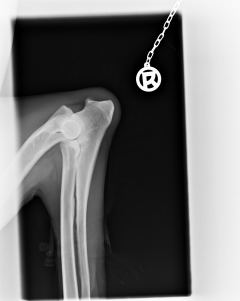

Bayou ist HD frei, ED frei und OCD frei.Beste Vorraussetzung für ein Deckrüde.

HD                                                           ED-Rechts                                         ED-Links                                                 OCD-rechts                                            OCD-links